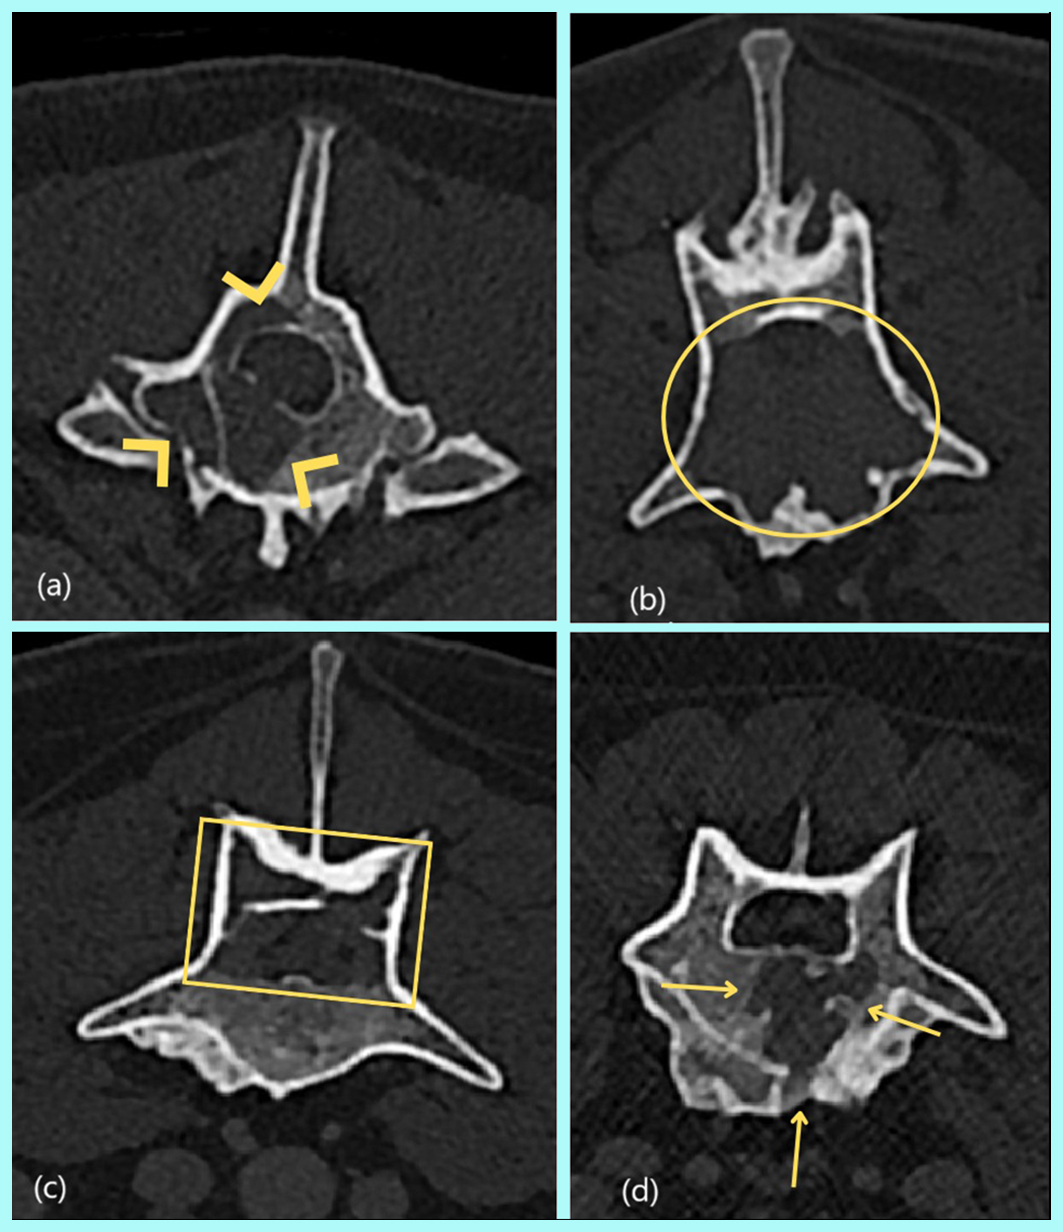

Resumo: O mieloma múltiplo (MM) é uma neoplasia linfoproliferativa rara em cães e gatos. Não há predileção por raça ou sexo e acomete animais na faixa etária de 8 a 14 anos. Os sinais clínicos associados ao MM são inespecíficos e incluem letargia, fraqueza e anorexia. O diagnóstico do MM é baseado na detecção de gamopatia monoclonal no soro ou na urina, lesões osteolíticas por meio de exames de imagem e no aumento de mais de 20% de plasmócitos na medula óssea por meio de citologia aspirativa ou biópsia por fragmento e histopatologia. O tratamento consiste geralmente no uso do melfalano combinado com prednisona que proporciona tempo médio de sobrevivência de 540 dias em cães. Este relato descreve a contribuição da tomografia computadorizada no diagnóstico do mieloma múltiplo em uma cadela, SRD, de 12 anos de idade que apresentava ataxia, fraqueza e redução da propriocepção em membros pélvicos.

Abstract: Multiple myeloma (MM) is a rare lymphoproliferative neoplasm in dogs and cats. There is no predilection for breed or sex and it affects animals between the ages of 8 and 14. The clinical signs associated with MM are non-specific and include lethargy, weakness and anorexia. The diagnosis of MM is based on the detection of monoclonal gammopathy in serum or urine, osteolytic lesions through imaging tests and an increase of more than 20% in plasma cells in the bone marrow through aspiration cytology or a fragment biopsy and histopathology. Treatment usually consists of the use of melphalan combined with prednisone, which provides a mean survival time of 540 days in dogs. This report describes the contribution of computed tomography in the diagnosis of multiple myeloma in a 12-year-old mixed-breed bitch who presented ataxia, weakness and reduced proprioception in the pelvic limbs.